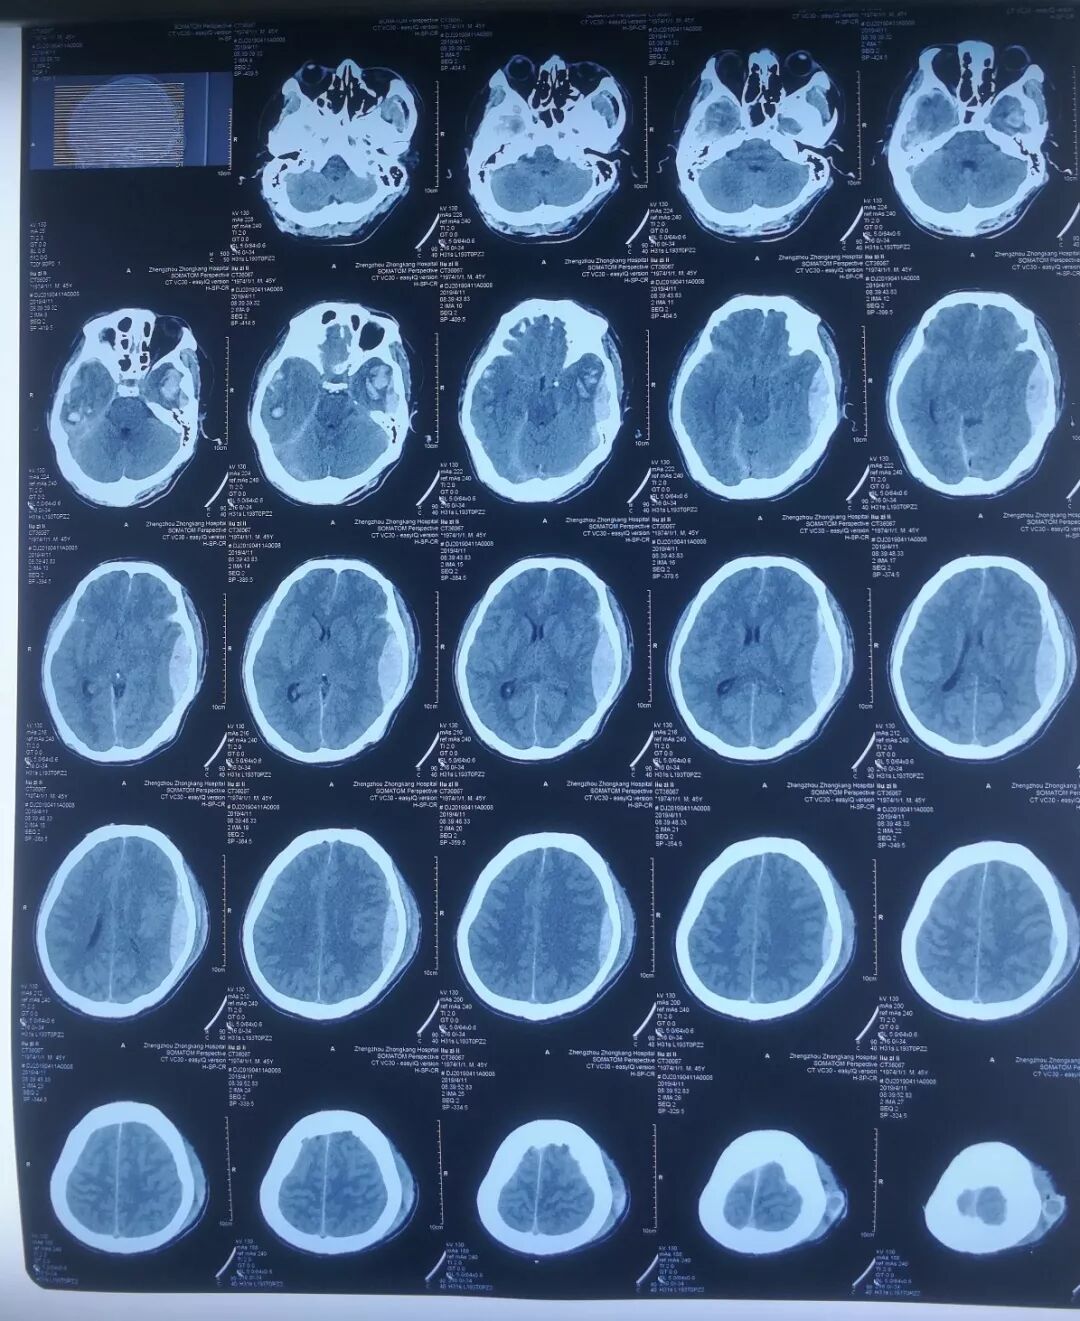

图片

(第二次手术后,刘某颅脑CT)

次日复查CT,右侧脑内其中一处脑挫裂伤加重,同侧大脑明显受压,仍需开颅手术。再次与患者家属沟通时,家属没有丝毫犹豫,表示全力配合,眼神里充满了信任。二次术后刘某病情逐渐稳定。